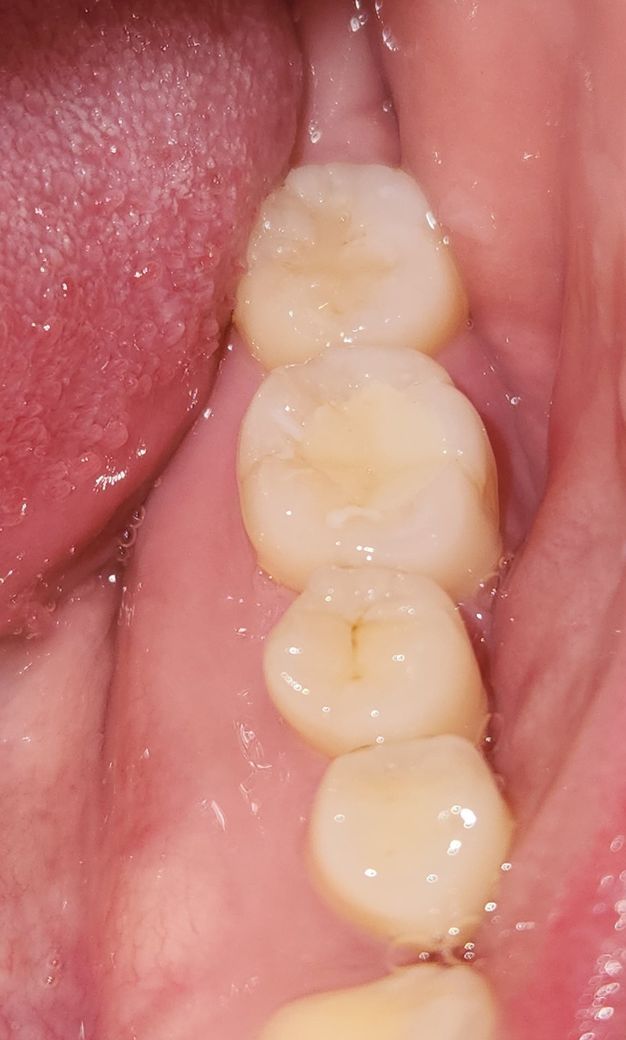

3월 13일날 치과에서 맨끝 어금니에 충치로 인해 홈이 파여있어서 레진으로 떼웠는데요.

교합면에 약간 선? 크랙같은게 생겨서 그런건지(사진에는 잘안보이지만 선이 있어요)

사진상 충치가 꽤 컸던게 아닌가 싶습니다

사진상으로는 크랙이나 2차충치는 보이진 않습니다. 충치가 깊어서 그럴 수도, 접착과정에서 문제가 있을 수도 있고 자극에 의한 통증이 오래 가는 것일수도 있습니다. 증상이 계속있다면 재치료를 해야할 수 있습니다.